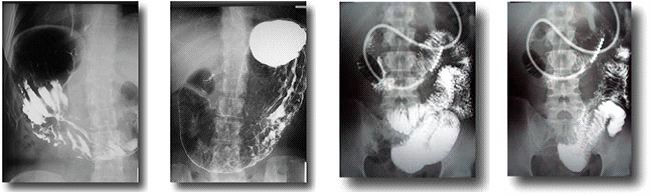

食道・胃・腸透視検査